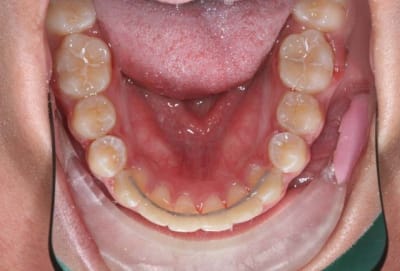

Img 1 xacnga - Eugenol

Img 2 siytdm - Eugenol

Img 3 ituagt - Eugenol

Img 4 r3tw6u - Eugenol

Img 5 z8ak0k - Eugenol

3°) phase

contention

@+ Bjc